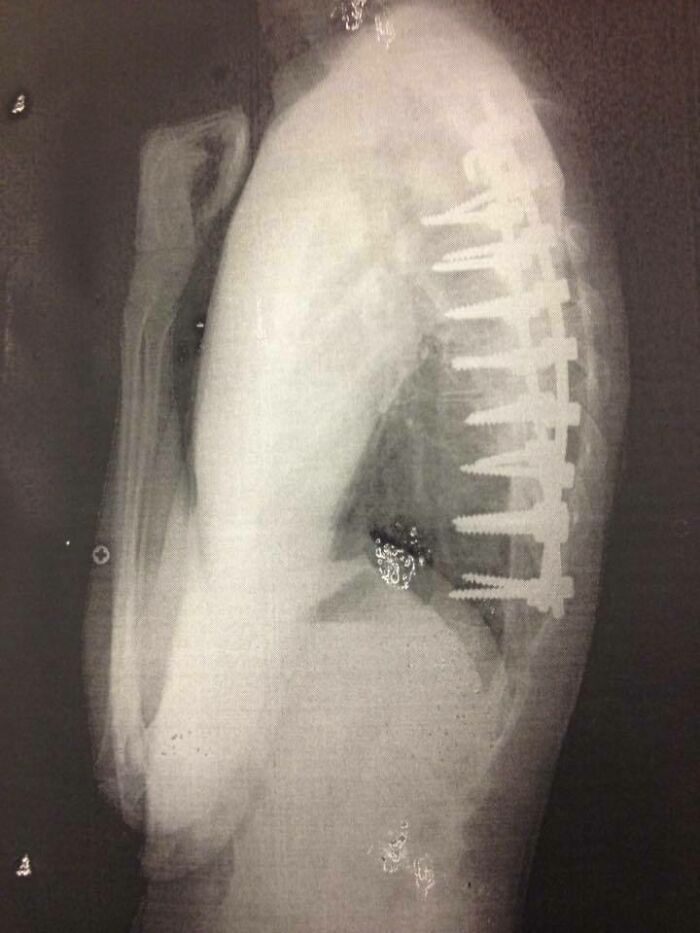

En mi cabeza, los tornillos de mi cirugía de fusión espinal parecían mucho más pequeños